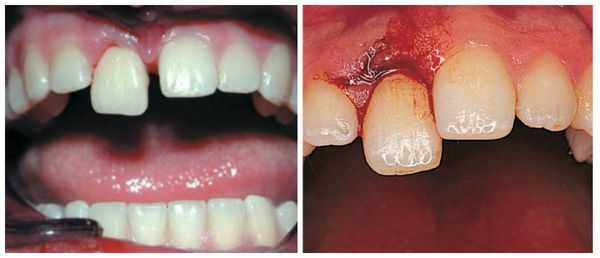

- Неполный вывих : боль усиливается при контакте с зубом, например во время приёма пищи; на слизистой оболочке полости рта имеются маленькие ранки, ссадины и гематомы; мягкие ткани отёчны; наблюдается смещение зуба в сторону и его значительная подвижность; вынужденное положение челюсти в связи с наличием болевых ощущений.

Неполный вывих характеризуется сохранением зуба в его лунке и сопровождается разрывом части волокнистых структур, окружающих и удерживающих зуб, либо растяжением волокон в той или иной степени. Для данной патологии характерно изменение положения коронки зуба и корня в зубном ряду по отношению к стенкам альвеолы. Зуб имеет неправильное положение вследствие смещения в вестибулярную ( в сторону губы) или оральную сторону, в сторону соседнего зуба или поворота вокруг оси. Это приводит к нарушению формы зубного ряда. Неполный вывих может сочетаться с переломом коронки, корня зуба или альвеолярного отростка.

Лечение неполного вывиха

Если у пациента наблюдается неполный вывих, то лечение начинают с проводникового обезболивания, после чего врач аккуратно репонирует (устанавливает в лунку) зуб. Репозиция проведена правильно, если при смыкании челюстей отсутствует соприкосновение травмированного зуба с антагонистом.

После проведённых лечебных мероприятий вывихнутый зуб иммобилизируют (обездвиживают). Для этого врач использует индивидуальную шину-каппу, изготовленную непосредственно на пациенте. В шину обязательно включают не менее двух здоровых зубов по обе стороны от неполного вывиха. Шину накладывают минимум на 5-6 недель.